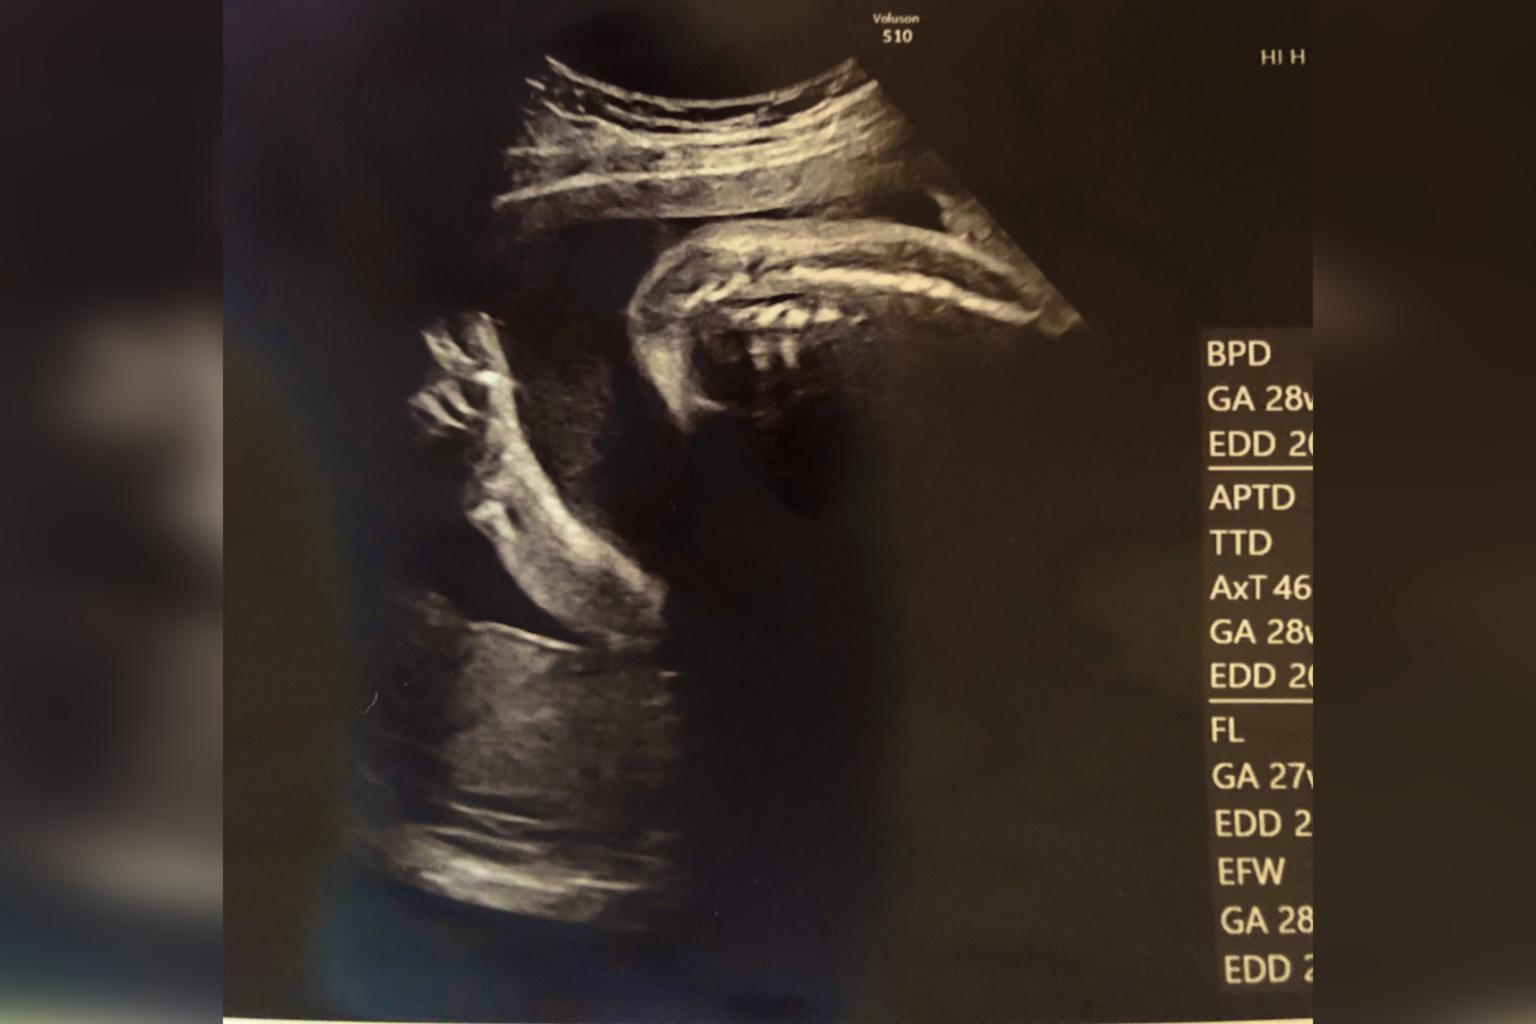

The 7-month pregnant woman considered her trip to the doctor as one of the best days of her life.

But for this Japanese mum-to-be, seeing her unborn child via foetal ultrasound was more than just enough to make her feel relieved from the Covid-19 threat, especially when the baby flashed a peace sign.

Reported by SoraNews24, a seven months pregnant woman considered her trip to the doctor as one of the best days of her life. Besides the fact that she's having a healthy pregnancy, Twitter user @madoka_people also shared that the baby even told her that "everything is going to be alright soon".

Along with her ultrasound result, where you can see her baby doing the "v" sign, madoka wrote in the caption:

"I'm currently seven months pregnant. I'm still feeling sad about the death of (Japanese comedian) Ken Shimura, who I liked so much, and feeling uneasy about what's going to happen with the coronavirus situation. But still, I had to go to the doctor for my pregnancy checkup. When I did, my baby flashed me the peace sign from inside of me. And now I'm cheered up."